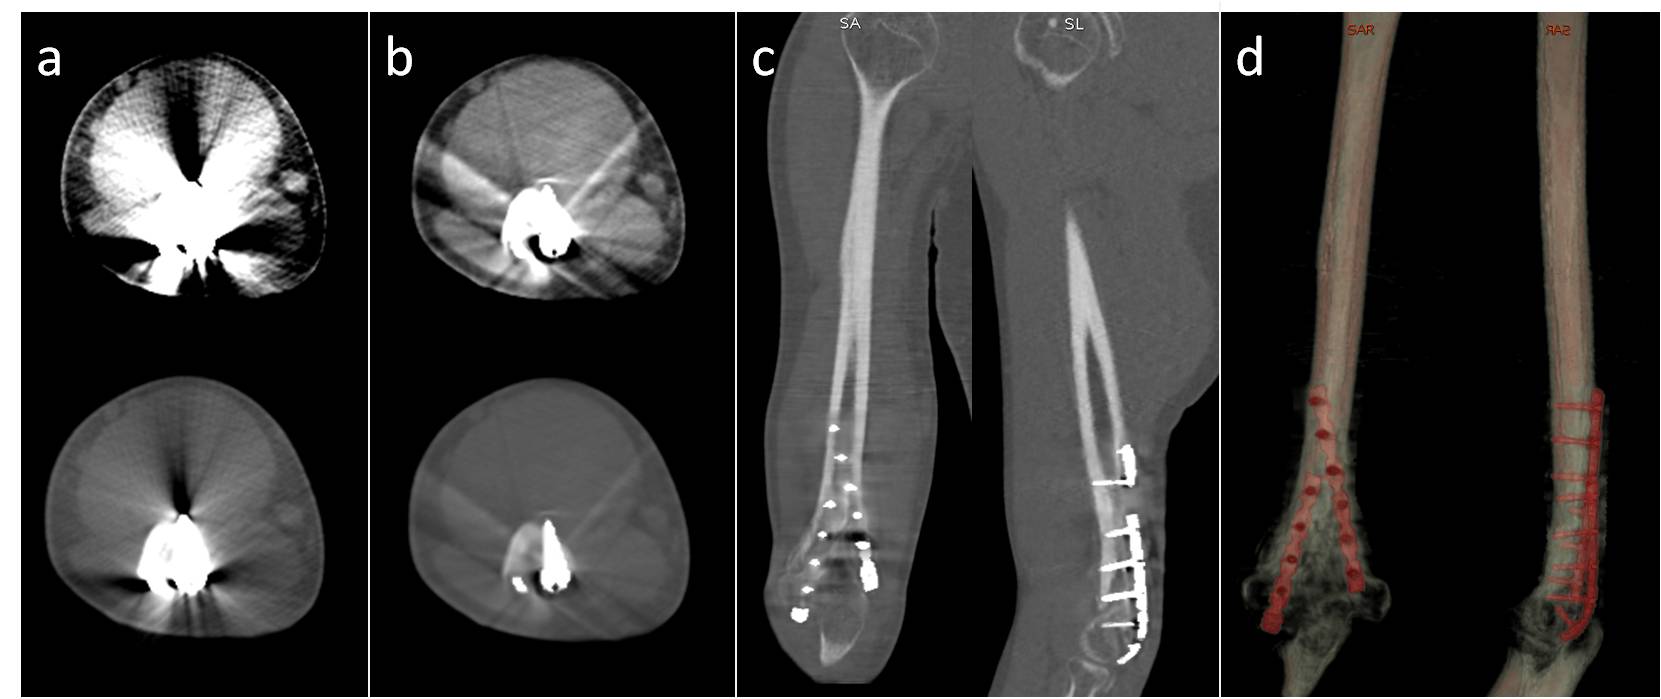

Tomografía computarizada de doble energía: nueva tecnología para la reducción de artefactos de metal. [Dual - Energy Computed Tomography: New technology for metal artifacts reduction.]